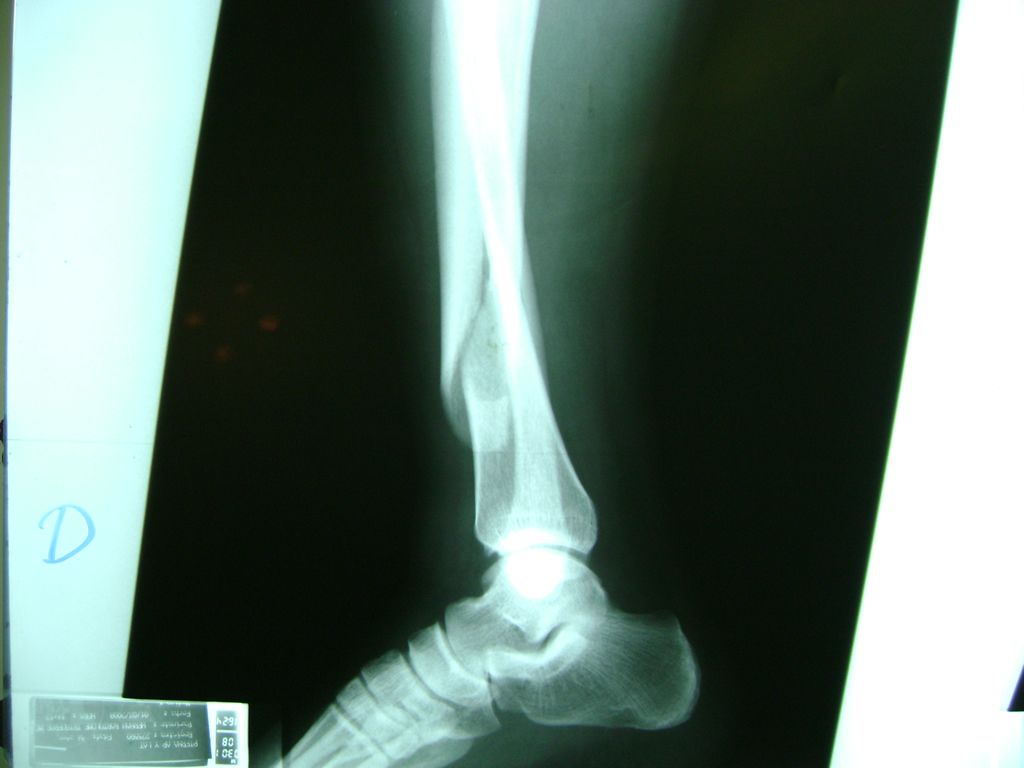

Calcaneo - Perone y Tibia

Aunque cada uno de estos huesos puede fracturarse por separado, normalmente la rotura es una lesión que se produce de forma conjunta

La mayor parte de las roturas implican a la parte proximal del hueso (parte del hueso próximo a la rodilla) o a la parte distal (parte del hueso cerca del tobillo).

Debido a la fina cobertura de piel que recubre la tibia y el peroné, las fracturas generalmente son abiertas, es decir, el hueso roto rasga la piel, atravesándola. Las fracturas de tibia y peroné generalmente se producen por un fuerte impacto o torsión.